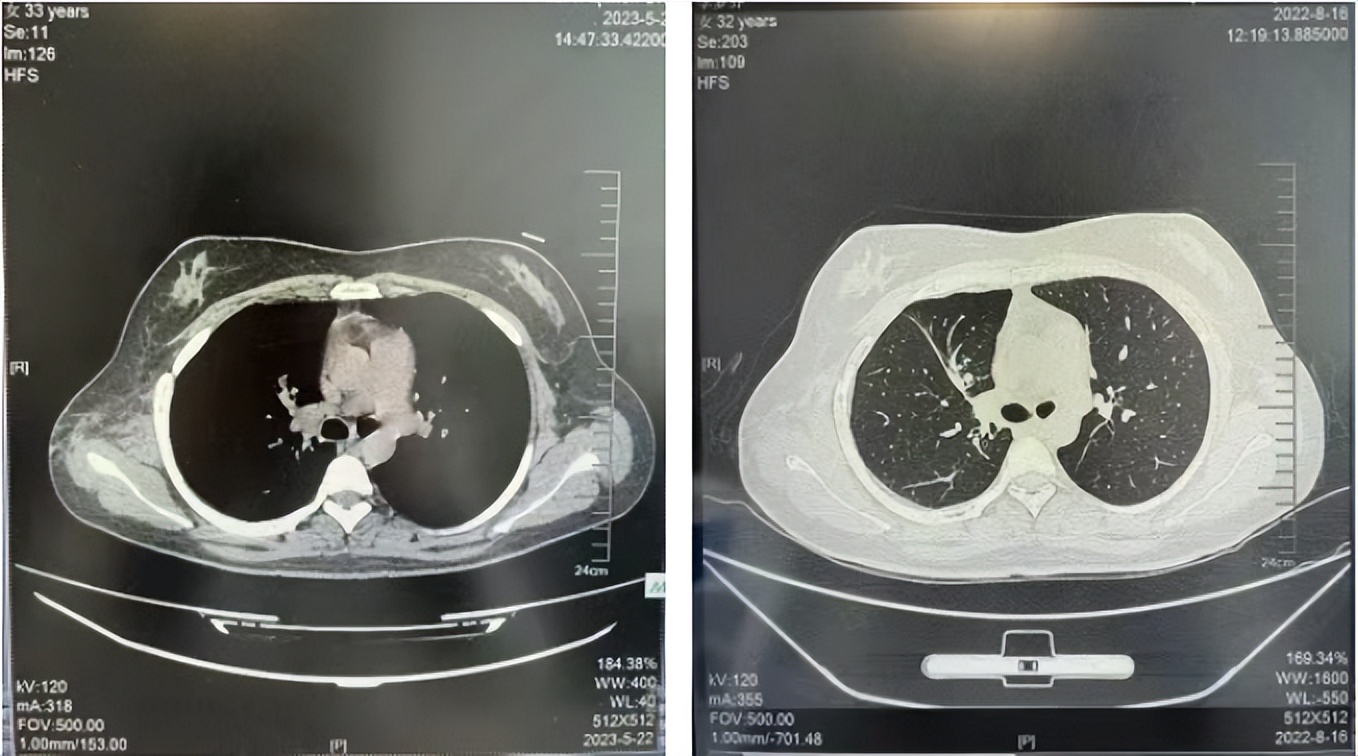

56岁,女性,无吸烟史饮酒史,既往体健。2023年02月患者体检发现肺占位性病变,胸部增强CT:右肺下叶后基底段结节;右侧锁骨上及纵隔内多发淋巴结肿大。PET-CT:右肺下叶周围型肺癌可能性大;1R、2L、3P、4R、4L及7组淋巴结转移可能性大。2023年02月就诊于本院胸外科行超声胃镜下纵隔肿物穿刺活检术,病理:结合免疫组化,符合肺腺癌。行NGS基因检测:EML4:exon20-ALK:exon20融合。PD-L1(克隆号22C3)TPS=55%。

2023年2月20日基线检查

2024年6月复查PR(最佳疗效)

2024年12月复查维持PR

2025年3月复查维持PR